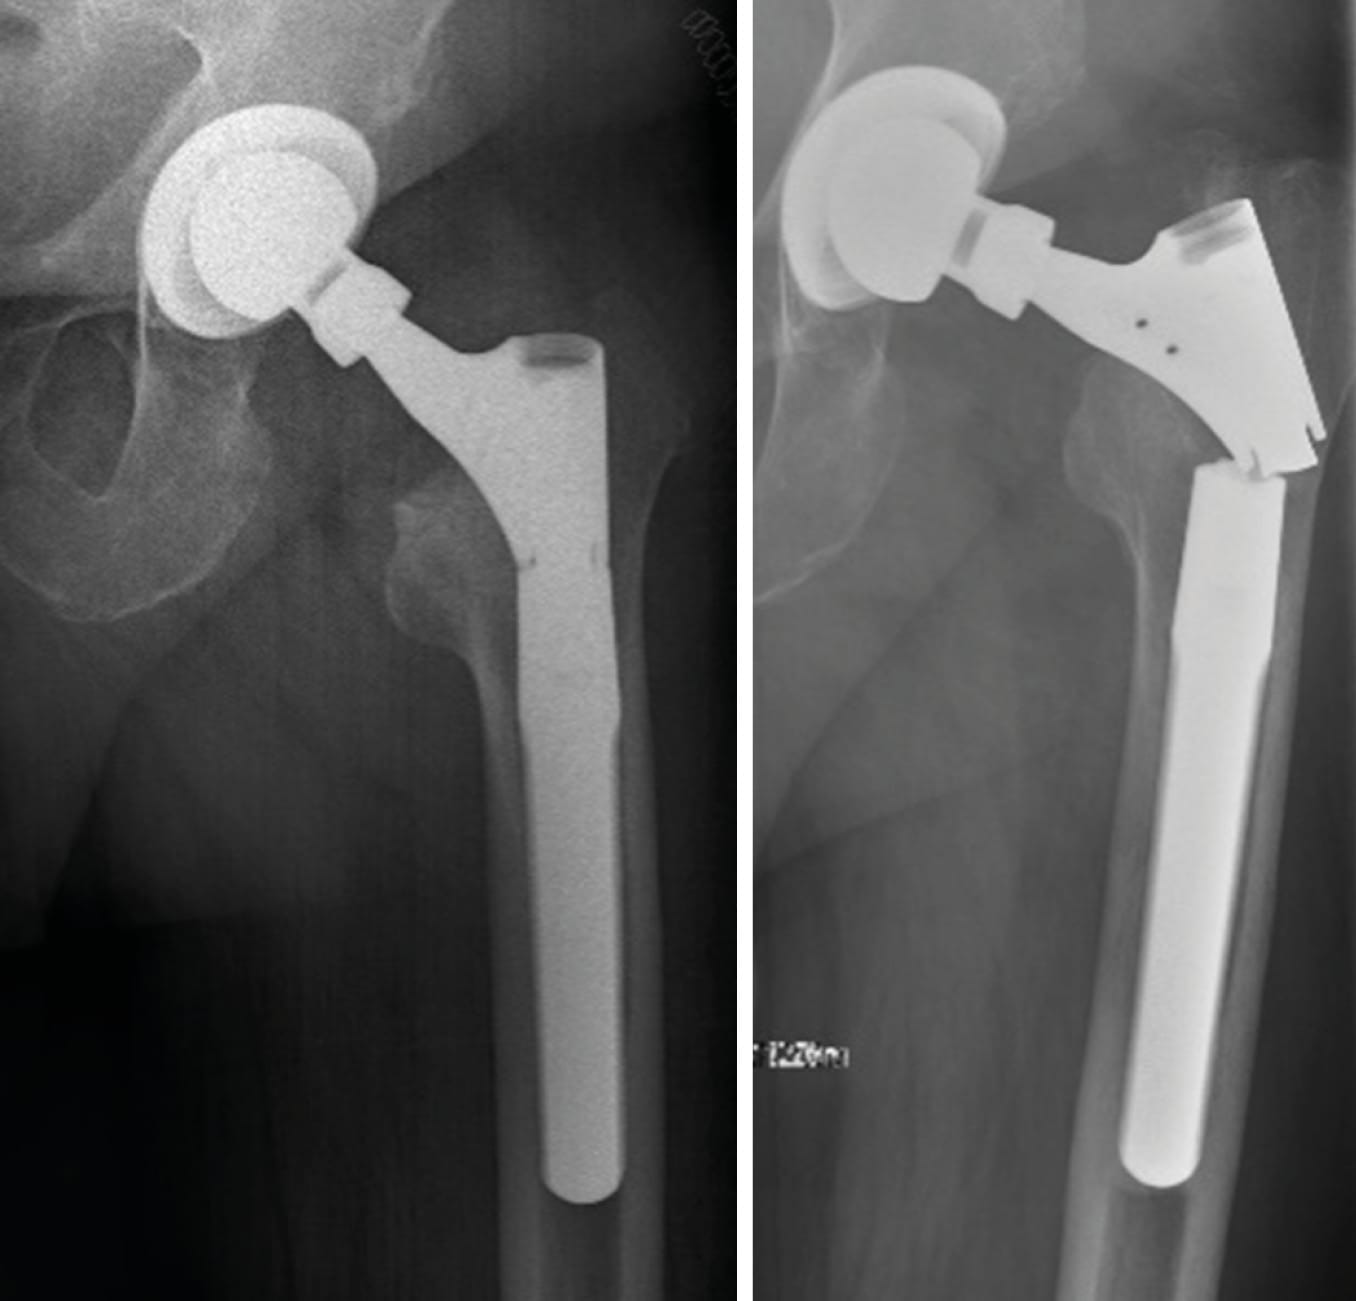

Case 5: Caution with application of extra-long adapters and modular revision stems (76-year-old male)

The patient had undergone femoral revision surgery due to aseptic stem loosening of the left hip 5 years ago. He subsequently developed failure of the taper junction of the modular revision stem. Most manufacturers advise against using heads larger than size L in combination with modular revision stems due to increased lever arms which may exceed material tolerance of taper connections.